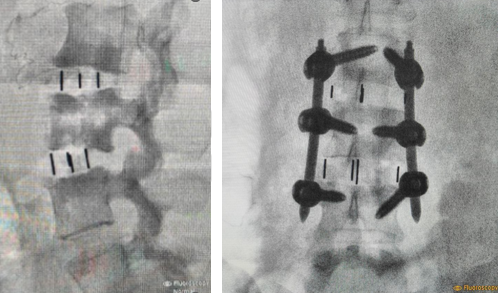

After Surgery Results

The surgeon removes the damaged disc or diseased bone, places a cage or bone graft between the vertebrae, and secures it with screws and rods. Over months, the bones heal together naturally. The surgical approach (front, back, or side) depends on the patient's specific condition and body type.